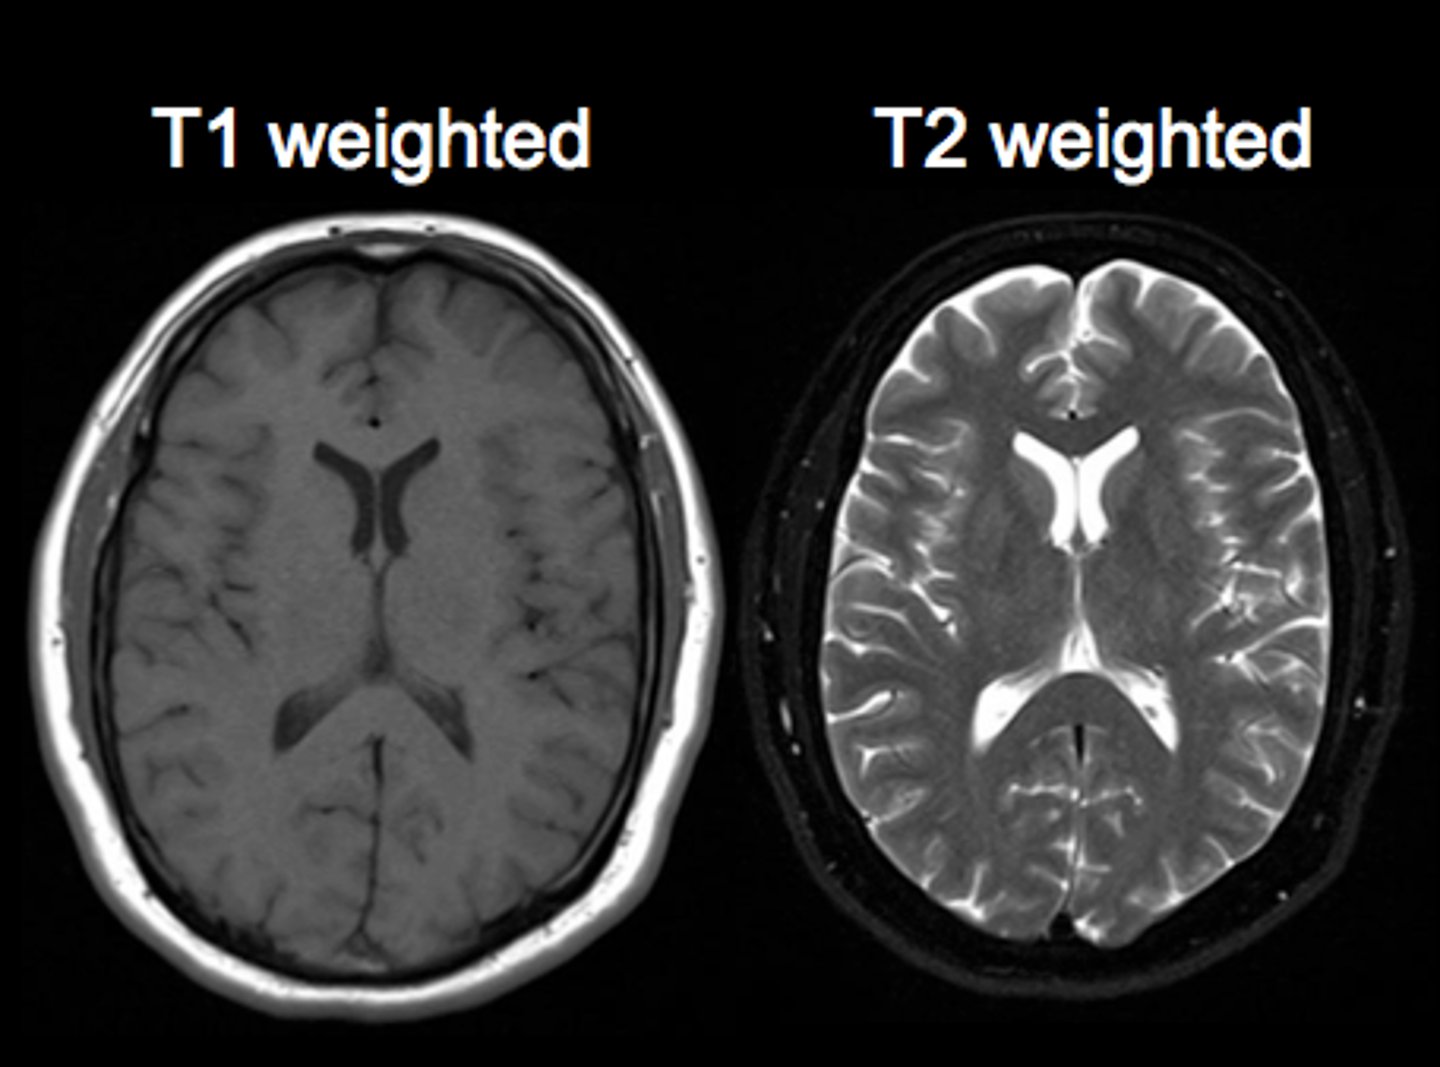

MRI T1 images

Fat is white

Water is dark

MRI T2 images

Fat is dark

Water is white

MRI flair images

Similar to T2, but CSF is dark